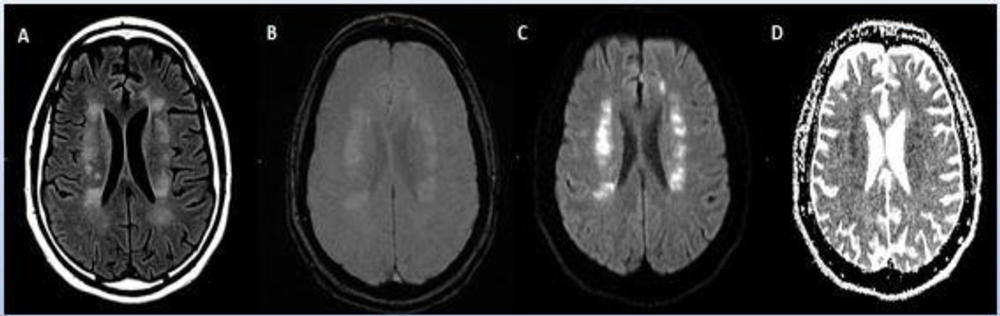

Figure 3. CT showing hemorrhage in a 68-year-old male patient with COVID-19 infection.

Figure 4. 62-year-old male with a past medical history of hypertension presenting with seizures.